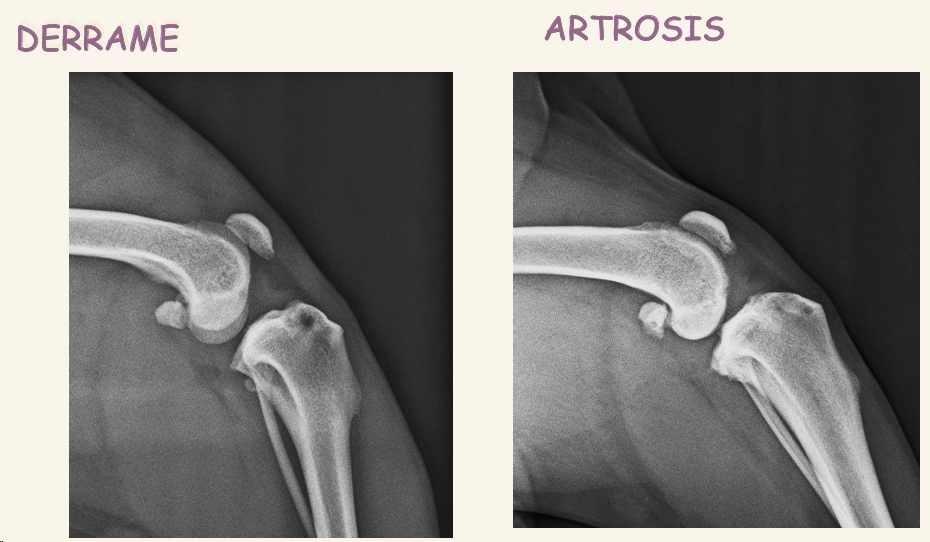

La rotura del ligamento cruzado anterior se ve siempre el desplazamiento de la tibia, patognomonico El primer signo es el derrame, en vez de ver color oscuro vemos zona mas radioopaca, gris

- Rotura del LCA o Ligamento cruzado anterior: TAMBIEN SE VE DERRAME ROTULIANO y desplazamiento de la tibia

- El primer signo radiológico es el derrame, se pierde radiolucidez en tejido entre articulaciones (Disminución de la almohadilla grasa subrotuliana) , se ve gris en vez de negro bajo la rótula